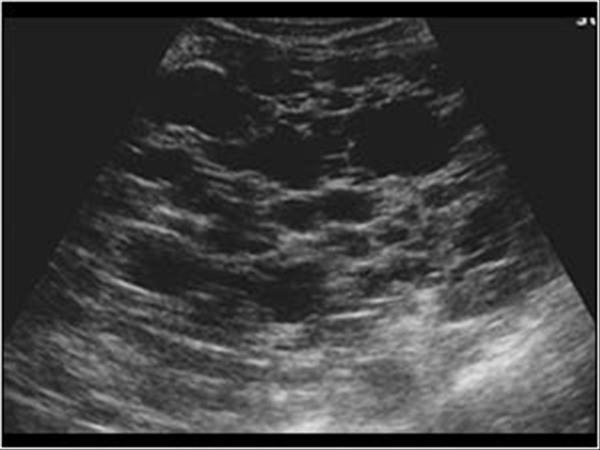

What is the sonographic appearance of fatty filtration?

Increased echogenicity

Enlargement

of the lobe.

Decreased penetration

Difficult to

image

Increased echo texture